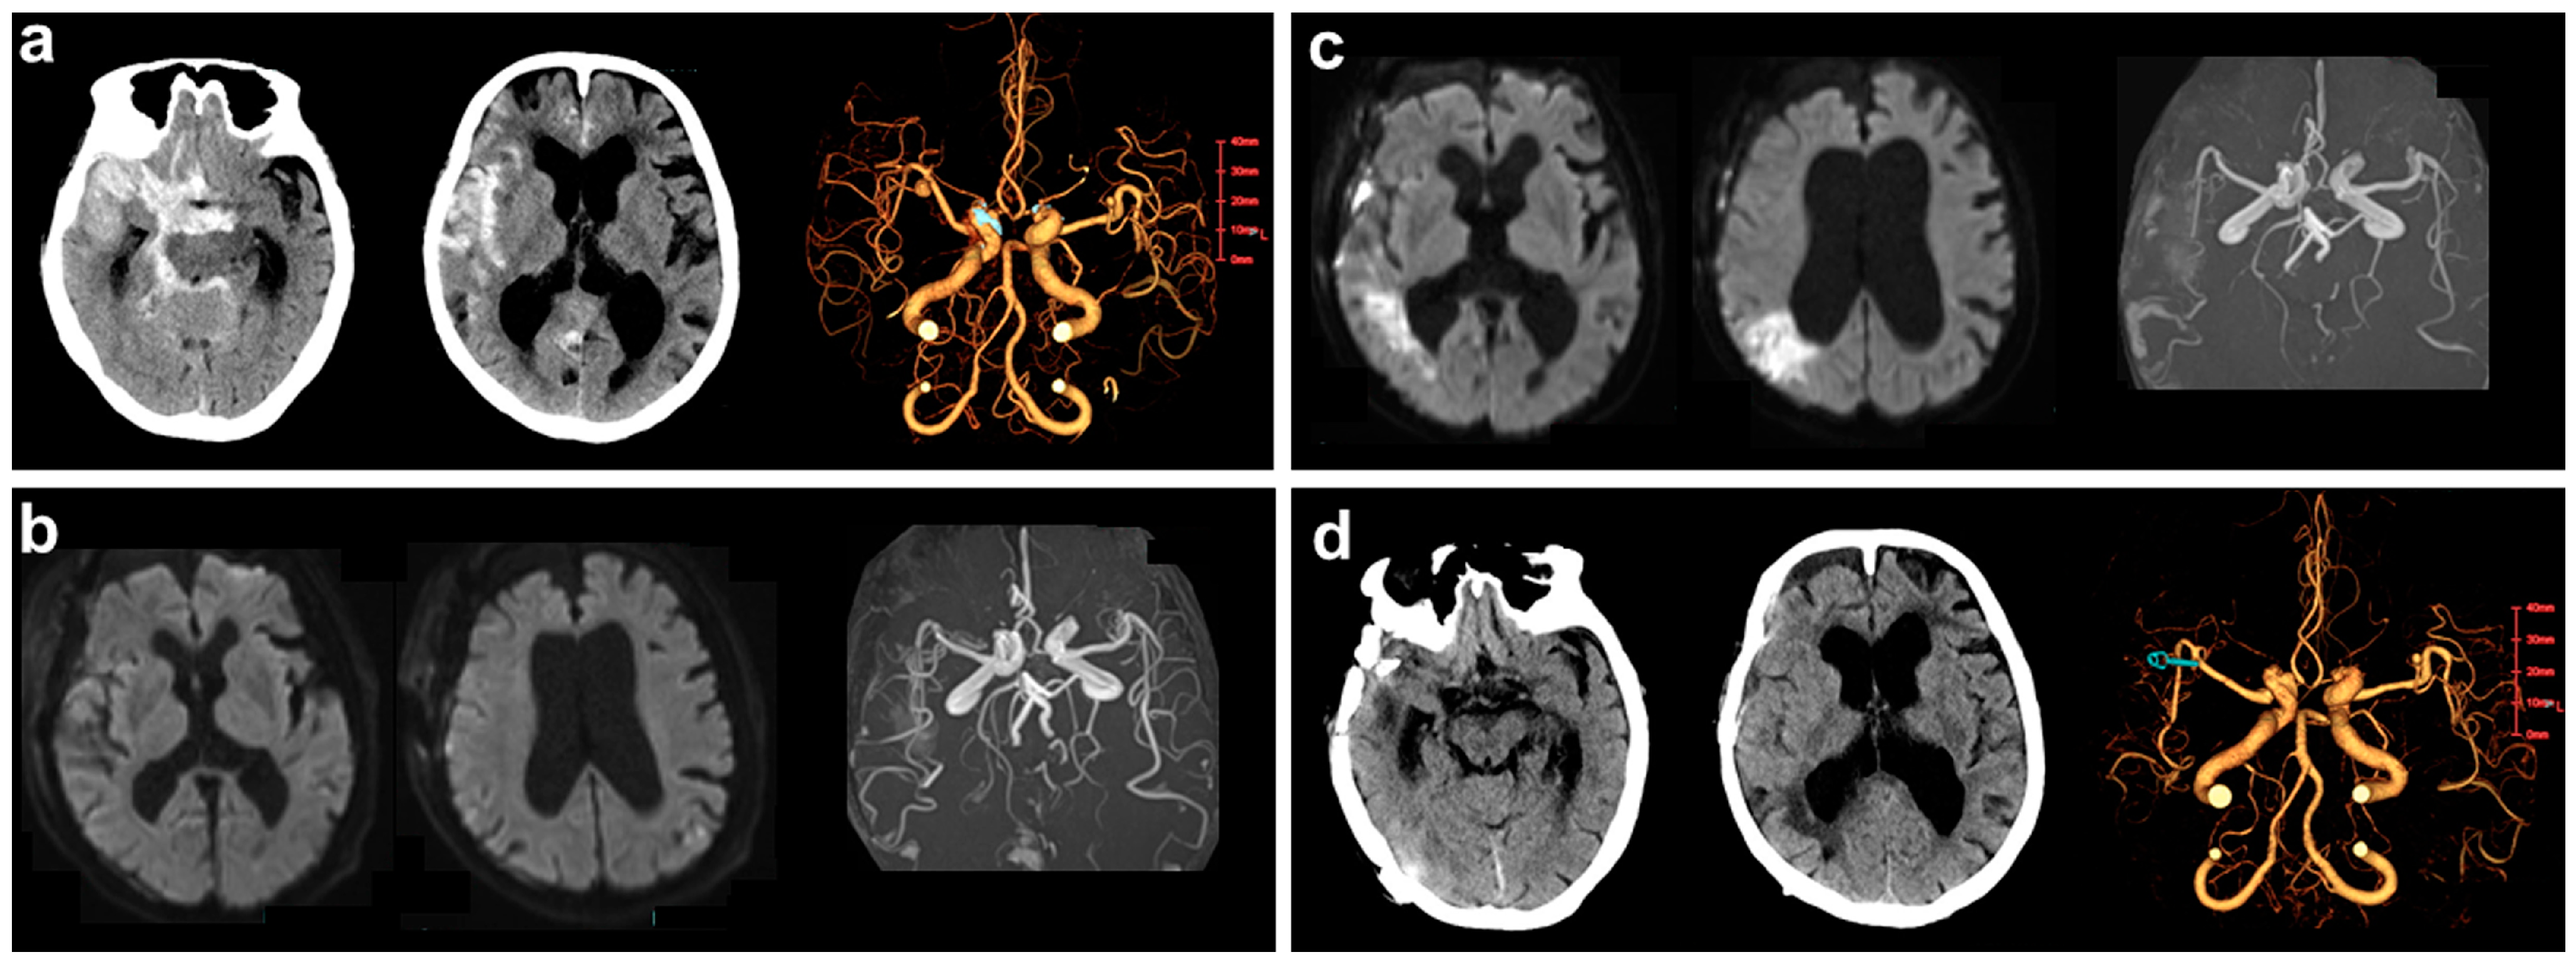

2.3. Illustrative Case